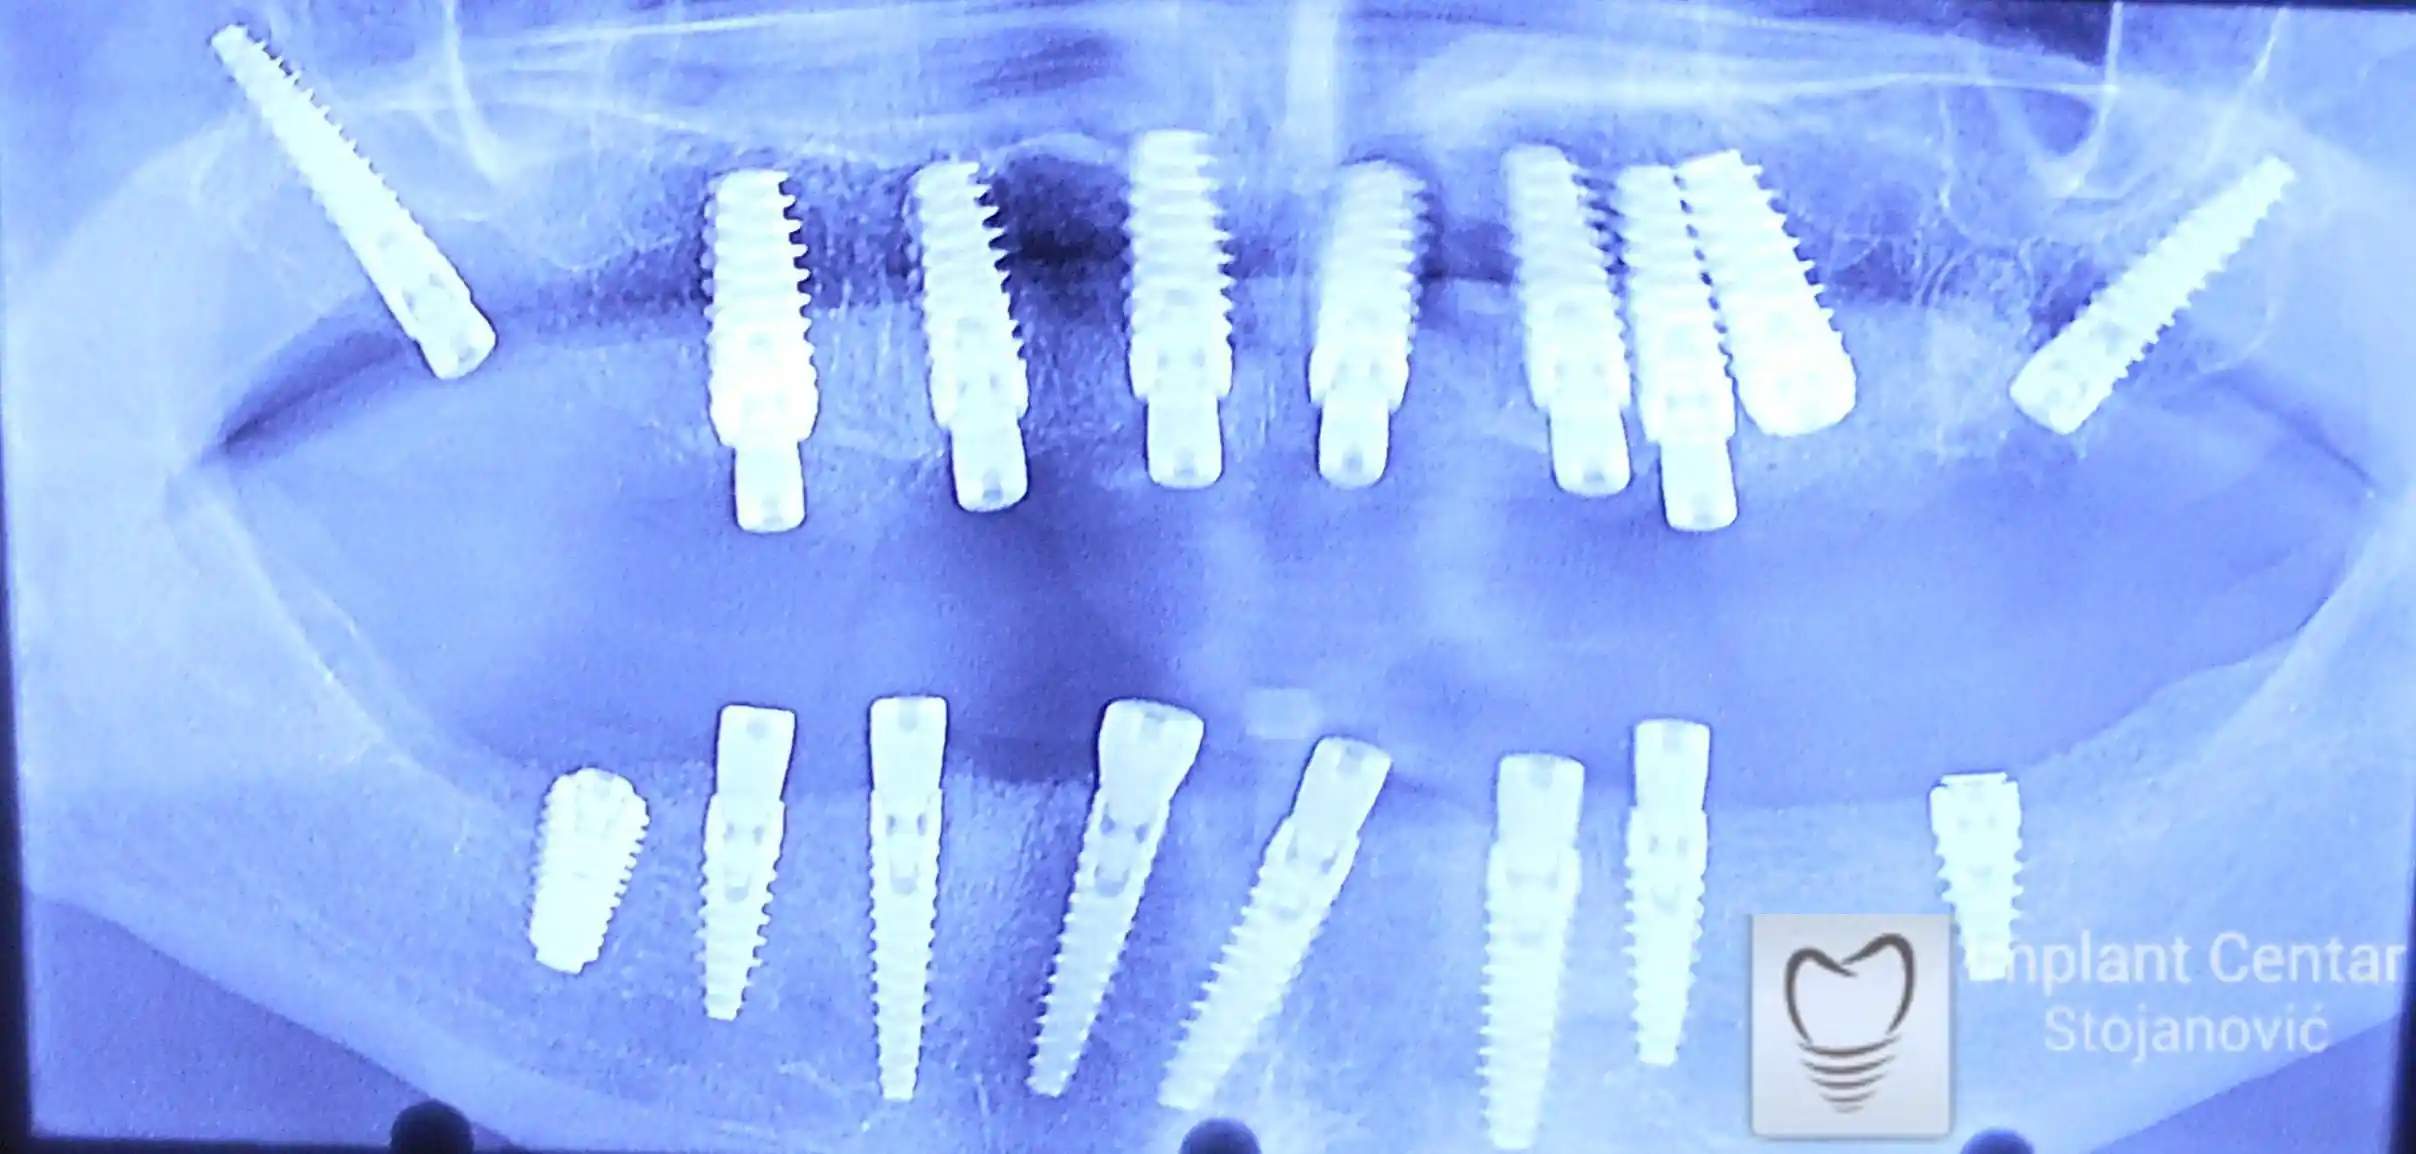

Na slici 1. i slici 2. prikazan je izgled pacijenta pre početka terapije – klinički i rendgenološki.

Nakon vađenja zuba, ugrađeni su implantati. Na slici 3 prikazan je ortopan snimak sa ugrđenim implantatima. Tokom perioda osteointegracije, pacijent je bio zbrinut fiksnim privremenim krunicama na implantatima, koje su izrađene samo dva dana nakon hirurške intervencije.

Na slikama 5. i 6. prikazan je izgled definitivnih cirkonijum-keramičkih mostova na implantatima.